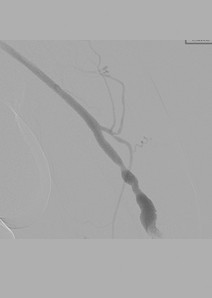

Fistulogram demonstrating thrombotic occlusion of a left brachiocephalic AV fistula (Note: arterial reflux of contrast).

Post 1st pass with AngioJet DVX Catheter (no thrombolytics used).